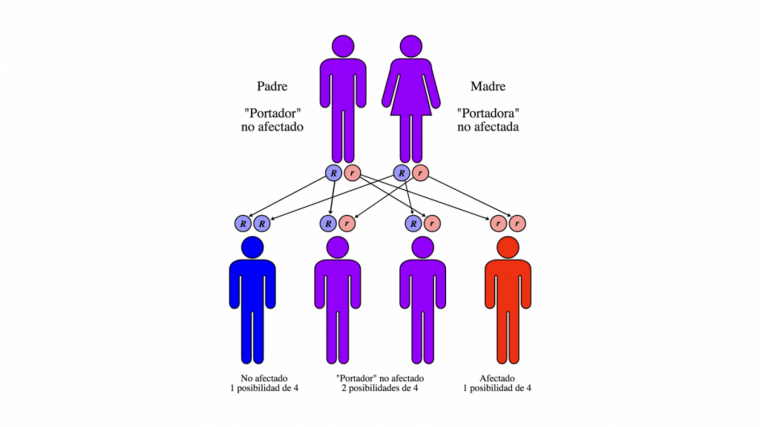

El origen de la fibrosis quística es una mutación genética que puede ser heredada de manera autosómica recesiva, lo que significa que para que pase de padres a hijos ambos progenitores deben ser portadores o pacientes de esta rara enfermedad

Para que una persona adquiera la mutación genética por parte de sus padres, debe heredar una copia del gen por parte de cada uno de los padres. Es decir, ambos deben de ser portadores o padecer fibrosis quística. Cuando el niño hereda una sola copia del gen se convierte en portador y puede transmitir el gen a sus propios hijos.